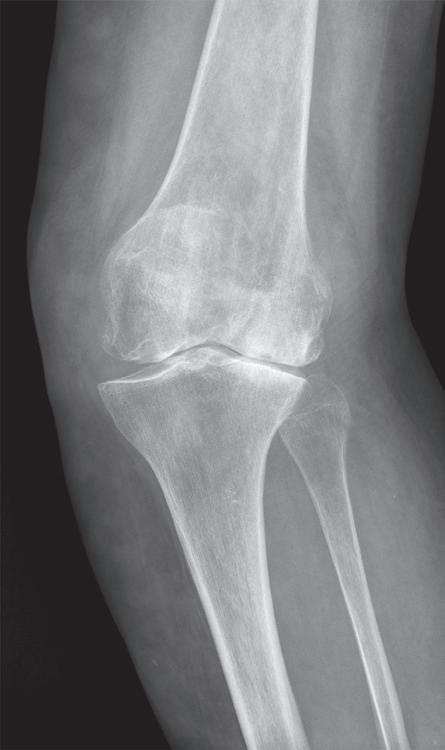

Obr. 19.11: Hemiartroplastika – předoperační (a, b) a pooperační rentgenový snímek (c, d)